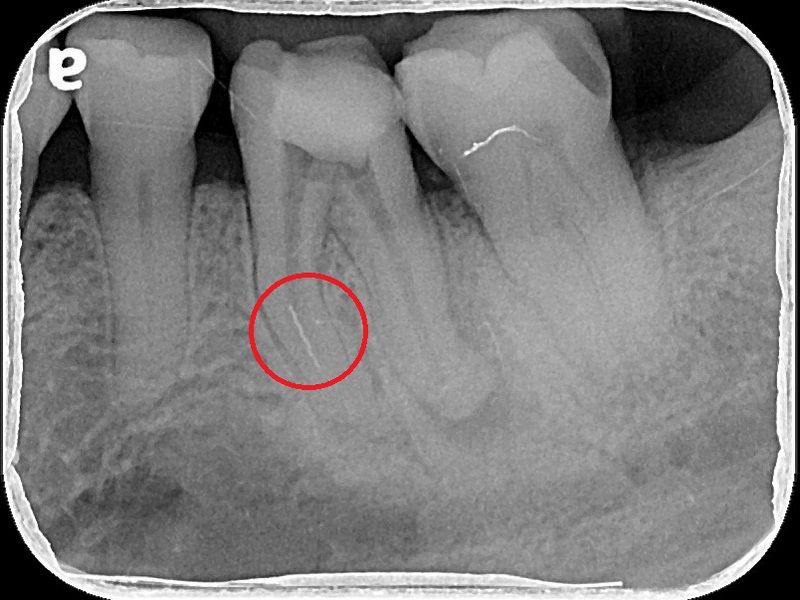

74歲的陳爺爺左下顎第一大臼齒處多年前曾接受根管治療,並裝上牙套,去年年中因為該處長了膿包,出現不適感,在坊間診所拆除舊牙套後,轉診來到台北慈濟醫院牙科部牙髓病科黃耀民醫師門診,希望在不拔牙的情況下解決膿包問題。透過X光及臨床檢查,黃耀民醫師發現膿包位在大臼齒頰側靠後方位置,且牙根底部有黑影表示有發炎狀況,左側根管內亦留存上次根管治療的分離器械。黃耀民醫師在顯微鏡視野下,利用超音波器械將根管內原有的馬來膠針封填物及分離器械移除,並徹底清潔根管系統,最後做緊密的封填。半年後回診,陳爺爺無任何不適,牙根尖的發炎狀況已經消失,膿包也未再出現,便返回原診所重做牙套。

根管治療是將根管系統做徹底的清創,藉由治療器械及殺菌藥水移除所有的牙髓組織及感染原,最後再用根管封填材料做緻密的充填,以維持清潔環境並減少病菌再次入侵感染的機會。黃耀民醫師提到,根管治療是為了增加保留牙齒的機會避免被拔除,但因為操作範圍狹小,且根管型態複雜多變,且可能還有根管彎曲、鈣化阻塞等現象,過去只能倚靠醫師臨床經驗及手感進行治療,容易有清創程度不足而導致治療效果不佳的現象。而牙科顯微鏡是現今輔助治療的新趨勢,可提供充分的照明及最大25至30的放大倍率,讓醫師更能看清楚根管系統,再搭配超音波器械,以最少破壞齒質的方式,做最大程度的清潔。一般而言,傳統根管治療的成功率約7至8成,而顯微鏡輔助根管治療的成功率可高達9成。

牙科顯微鏡除了適用於複雜型根管系統的治療外,在根管穿孔修補、根管內分離器械移除、齒裂檢查、活髓治療等方面都扮演重要的角色。另外,在根尖手術或牙周病手術時若能搭配顯微鏡,則更能有效清除掉肉眼不易看見的發炎感染組織,提高治療的成功率。牙周病科蘇穎珊醫師也表示牙科顯微鏡也是牙周治療的新利器,除了可以精細觀察牙周病灶以及精確找到致病因子進行有效的清潔,在手術治療上藉由放大設備可以進行微創治療減小傷口,縮短癒合期,提高治療的效率。